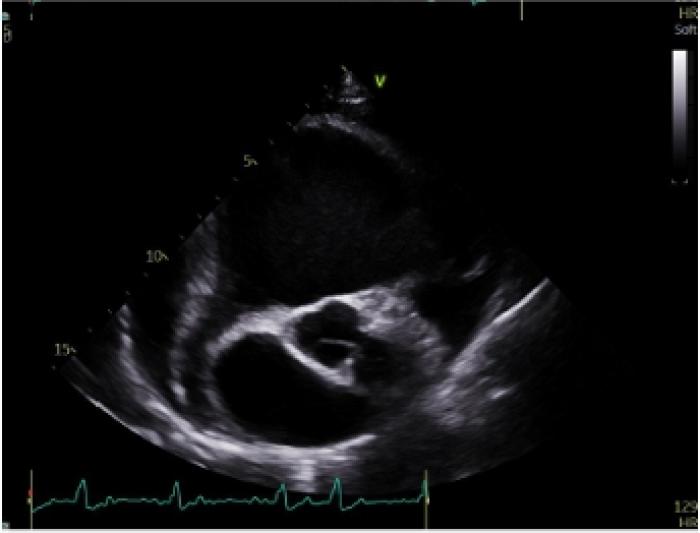

El examen ecocardiográfico muestra dilatación muy marcada del corazón derecho, con aplanamiento de los septos interauricular e interventricular. Además, el corazón izquierdo se muestra comprimido debido al agrandamiento del corazón derecho (Figura 3A-B). Durante el examen, se detecta displasia de la válvula tricúspidea, con una velocidad de regurgitación tricúspidea (RT) de 3.2 m/s (referencia <3 m/s), y mostrando la válvula una morfología engrosada y retraída. Además, la válvula mitral presentaba un engrosamiento leve.

Figura 3. (A) Corte paraesternal derecho de cuatro cámaras en el que se aprecia la dilatación marcada de las cámaras cardíacas derechas y la presencia de derrame pericárdico. (B) Eje corte por a nivel de base cardíaca, este corte se realiza por ventana paraesternal derecha con un eje transversal. En esta imagen se puede apreciar la dilatación marcada de la aurícula derecha.

En el examen por Doppler color, se detecta flujo turbulento severo a nivel de la válvula tricúspide (Figura 4A) y moderado en la válvula mitral. A nivel de la válvula pulmonar se detecta una leve insuficiencia, aunque muestra una apariencia normal. Las velocidades aórticas se encuentran por encima del límite normal, con un valor de 2.23 m/s (referencia: <2 m/s). La función sistólica se encuentra disminuida, con una fracción de acortamiento (FA) del 13.77 % (referencia: 28-45 %) y una fracción de eyección (FE) del 29.34 % (referencia: 40-75 %) (Figura 4B).

Durante el examen también se detecta la presencia de derrame pericárdico leve (ver Figuras 3A-B y 4A-B) sin evidencia de taponamiento cardíaco. El ECG durante el estudio ecocardiográfico confirma la presencia de fibrilación atrial.